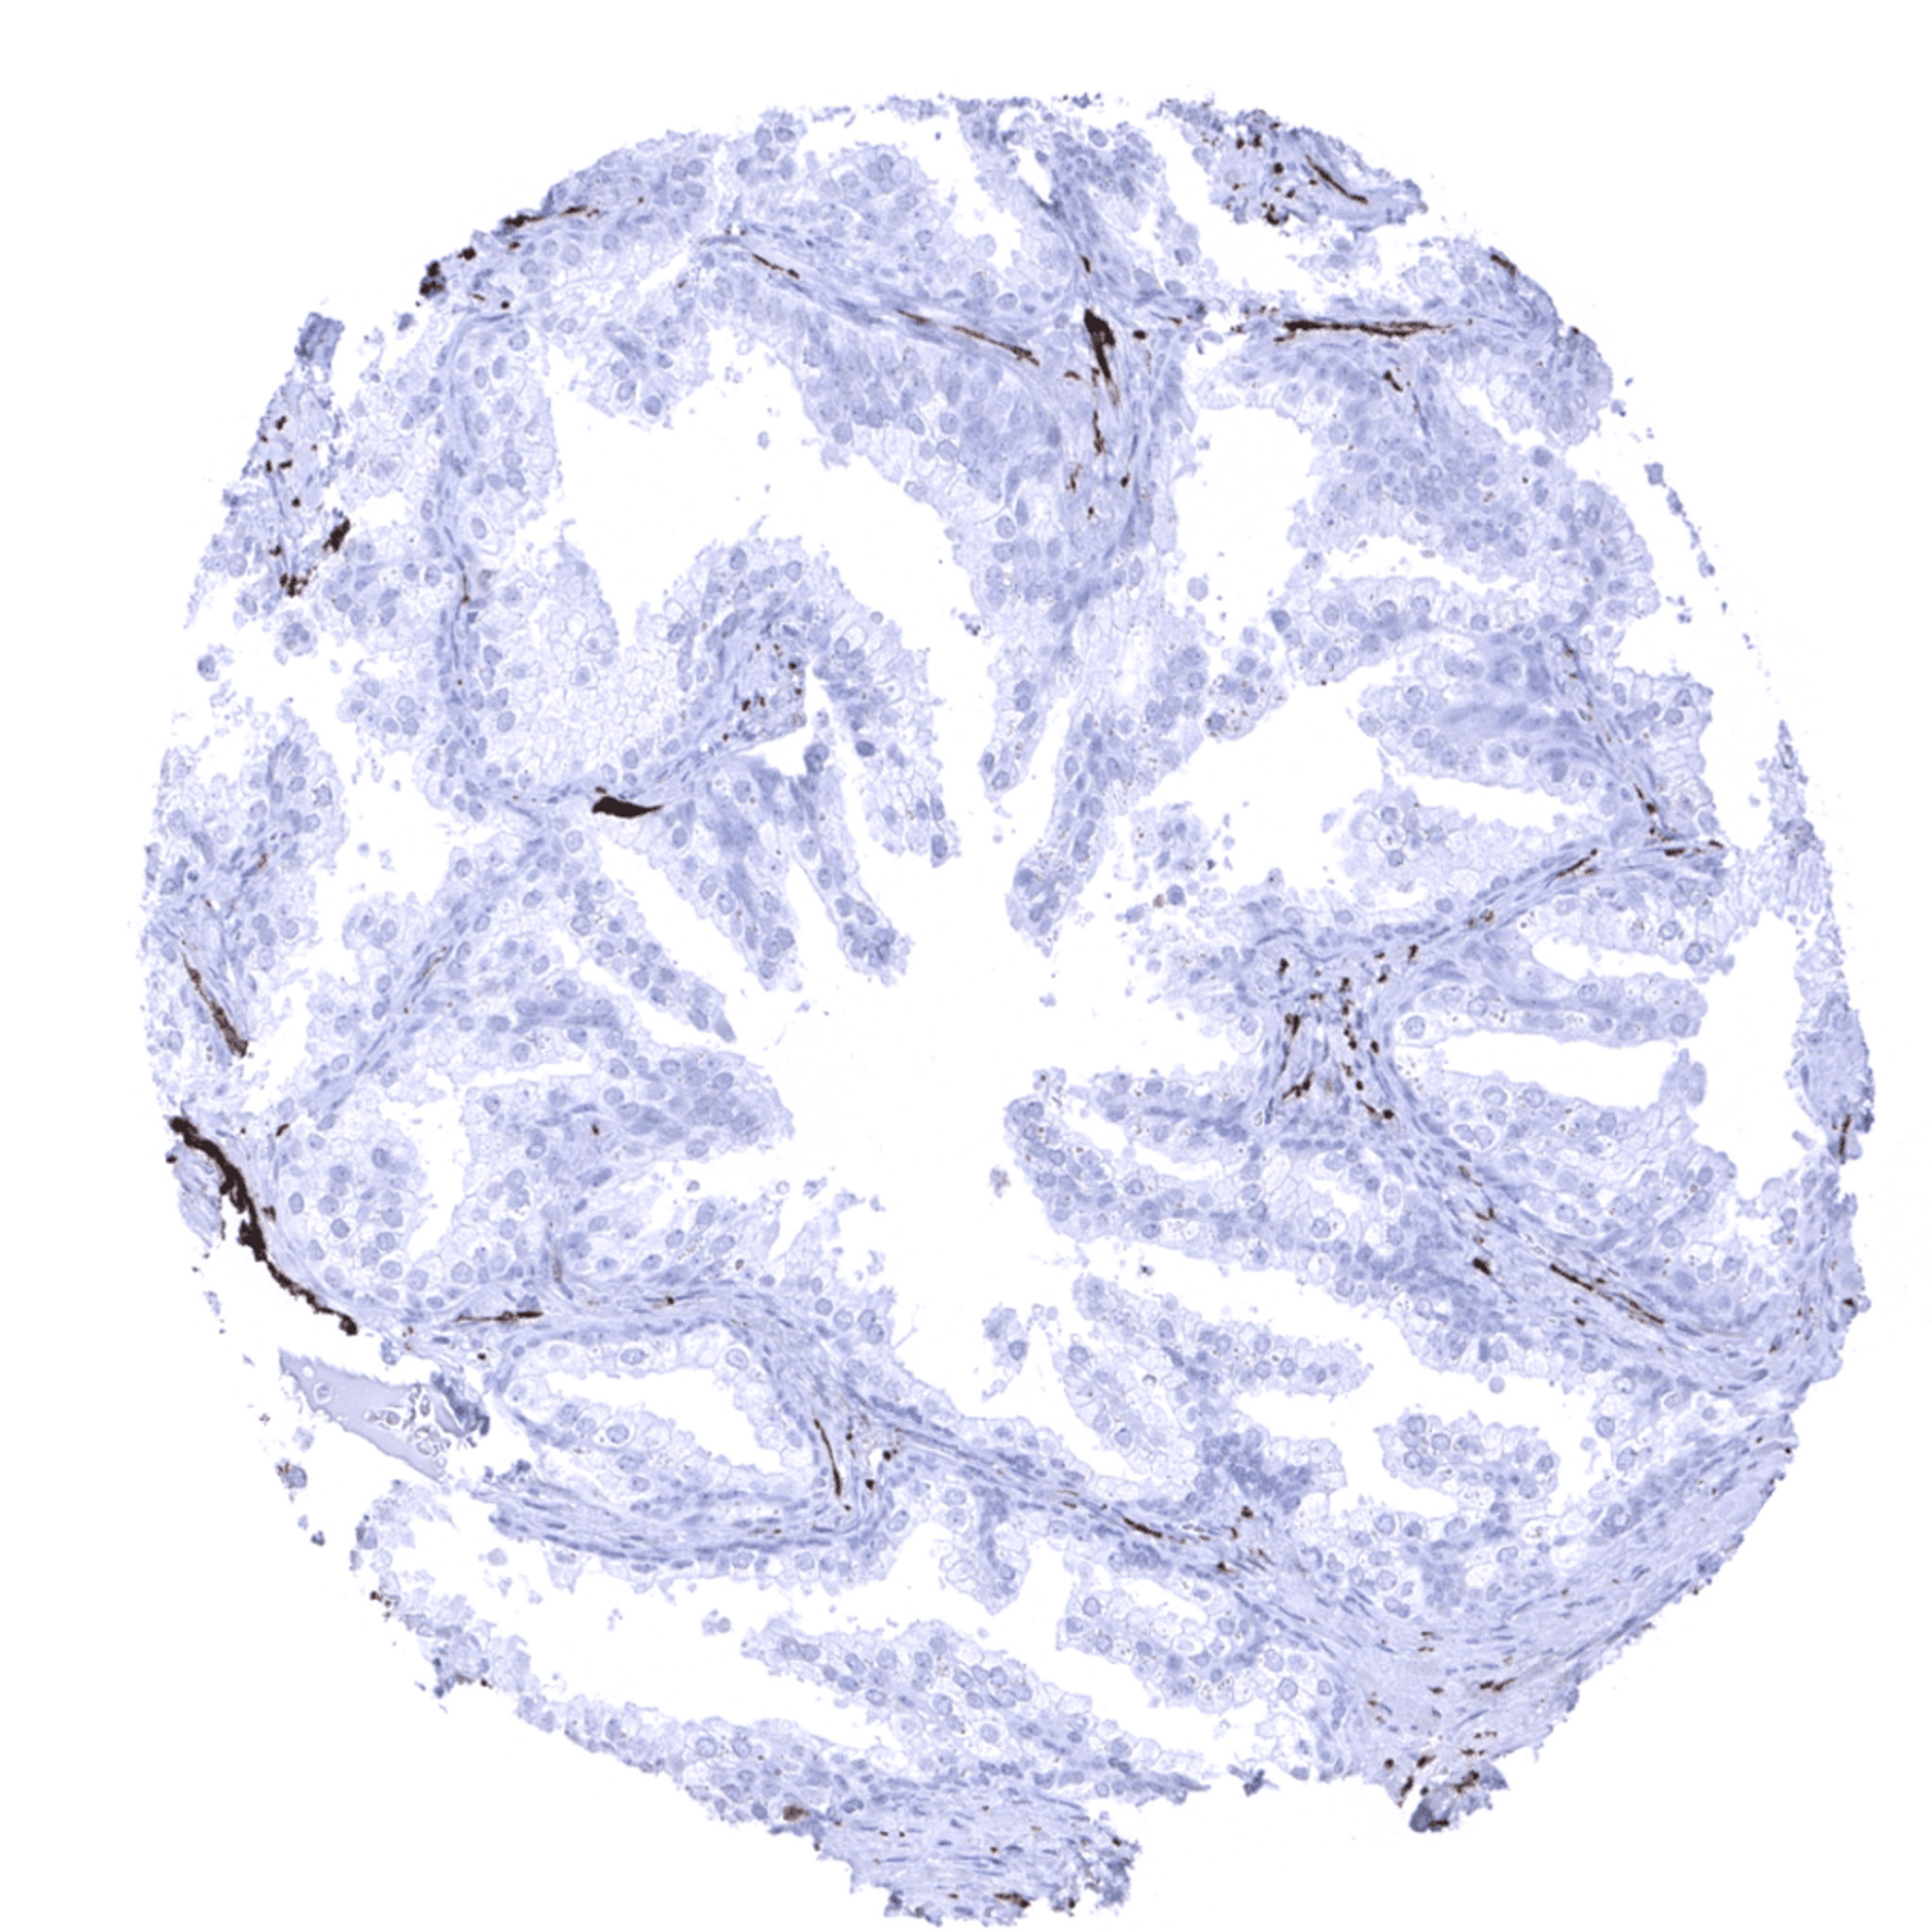

Colon descendens, mucosa

Colon descendens, muscular wall – Strong PGP9.5 immunostaining of nerve fibres and ganglions in the muscular wall.